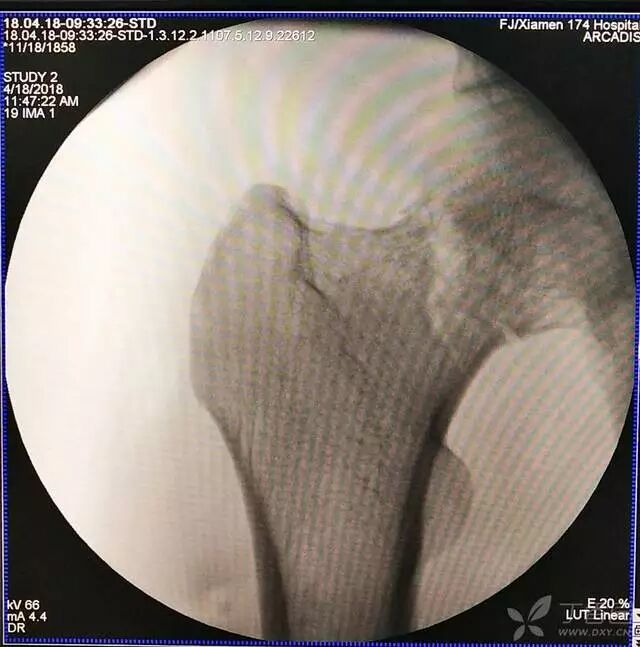

1. 对于难复性股骨颈骨折,术前应做好切开复位的准备,该患者复位三次都不太满意。

2. 倒数第二次的复位仍是欠缺一点

3. 再努力一把就基本成了